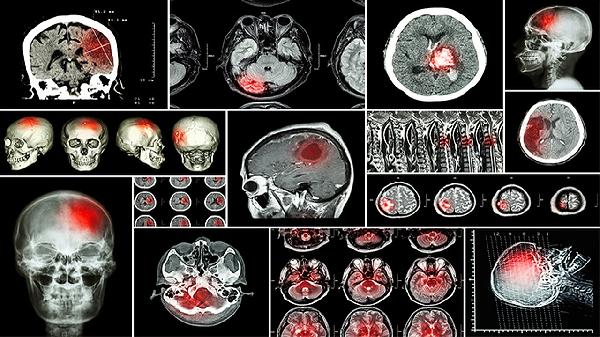

高压氧对治疗脑损伤有帮助吗

高压氧对治疗脑损伤有一定帮助,能够改善脑组织缺氧状态并促进神经功能恢复。高压氧治疗通过提高血氧分压和增加组织氧储备发挥作用,适用于部分脑损伤患者。

高压氧治疗可改善创伤性脑损伤患者的脑水肿和颅内压升高。在标准大气压下吸入纯氧可使血浆溶解量显著增加,促进受损脑细胞的代谢修复。临床观察显示早期介入高压氧能减少继发性脑损伤,缩短昏迷时间。治疗通常需要10-30次为一个疗程,压力控制在1.5-2.0个大气压范围内。对于缺氧缺血性脑病、脑挫裂伤等疾病,配合高压氧治疗可提升康复效果。